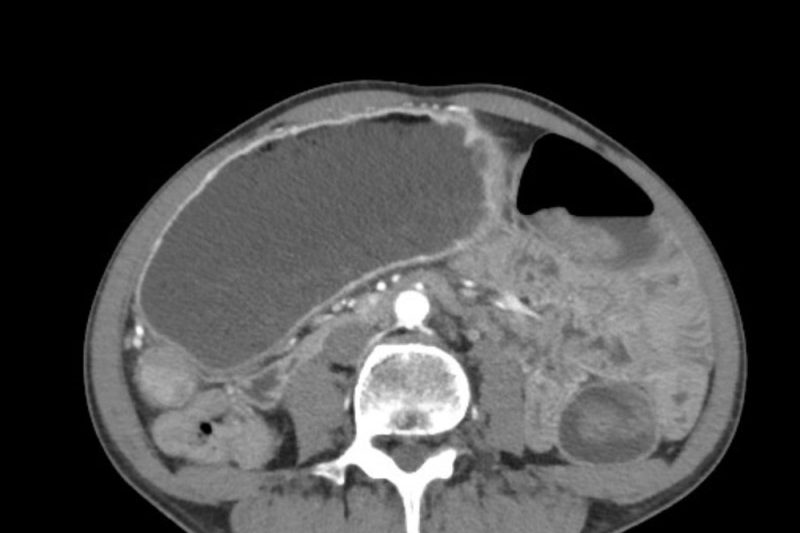

Leziune hipodensă la ficat: ce trebuie să știi despre această situație?

Un rezultat imagistic care menționează o „leziune hipodensă la ficat” poate crea neliniște, mai ales dacă nu ai simptome sau...